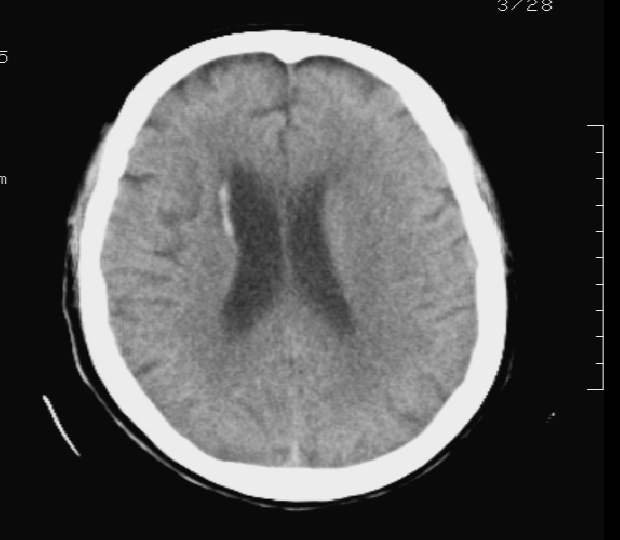

标题: CT19079:出血?钙化?(已证实为出血) [打印本页]

标题: CT19079:出血?钙化?(已证实为出血)

男 58岁 双下肢无力个一天 糖尿病患者

测ct值 67左右

患者今日行mr检查:右侧室管膜下见条状短t1长t2 flair呈高信号影, 证实为出血

灶周水肿,ct值较低,考虑室管膜下出血

考虑室管膜下出血;建议短期复查,排除钙化灶。

考虑室管膜下出血,因为旁边有水肿。